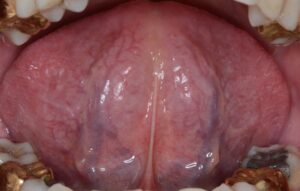

コロナが蔓延してからここ2年間患者さんの舌の状態を診てきましたが、ワクチン接〇者もそうですが「シェディング」の影響を受けた方の多くが「瘀血」という血液循環障害に陥っていました。舌の裏側の血管が黒く浮き出ているので、誰でもすぐ自分が「瘀血」かどうかを知ることが出来ます。

下、瘀血の人の舌(裏に黒い血管が浮き出る)